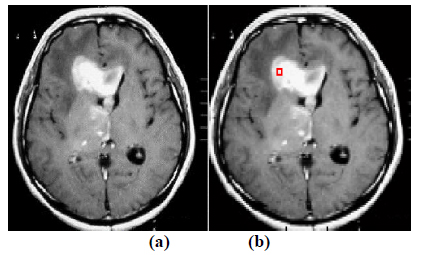

The experiment is conducted using brain web and Digital Imaging Communications in Medicine (DICOM) database [27, 28]. These database consists of T2 weighted MR images of sizes with tumor history. Pre-processing of an original MR image is an important step before applying the segmentation algorithms. In this case, the original MR image is pre-processed by applying median filter. Median filter removes salt and pepper noise which is very common in MR images of the brain. After removing the noise, wavelet transform is applied for multiresolution analysis to enhance the features of the image. Then, spatial FCM technique is applied to the multiresolution image. This technique minimizes search area to a very small region by creating cluster number k parameter for termination and max iteration values. Finally, these tumor clusters are segmented by level set evolution algorithm [29-39]. The following experimental results demonstrate the segmentation process used in the proposed methodology. In this experiment, two MR images having tumor in different locations of the image were selected to test the proposed segmentation algorithm. In Fig. (3), the original image and contour initialization for MR image 1 is shown. The contour evolution and final segmentation are depicted in Fig. (4). Similarly, Fig. (5) shows the original MR image 2 and the initial contour position. As the iteration values increases, the contour evolves towards the tumor boundary.